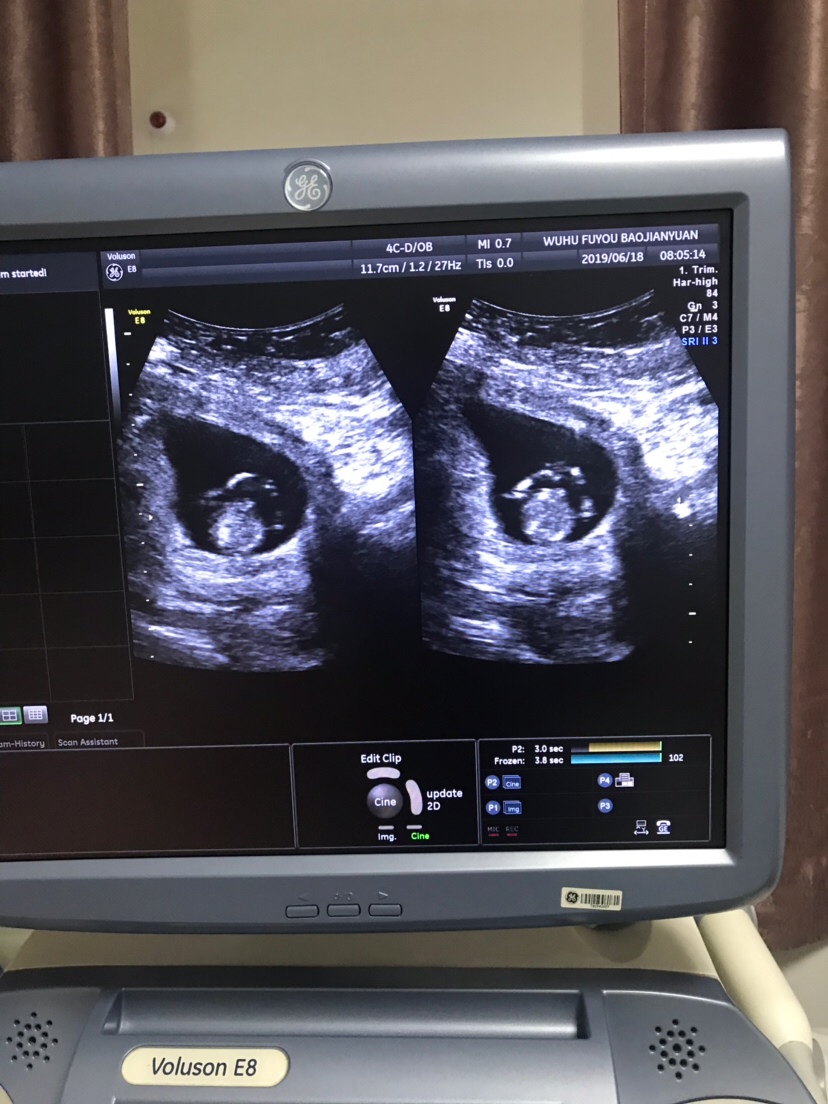

孕8周+3天